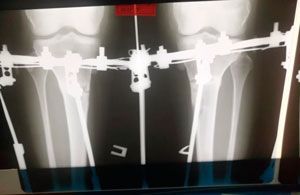

рентген в 60 дней

IMG_4850-06-08-19-08-10.JPG

IMG_4849-06-08-19-08-10.JPG